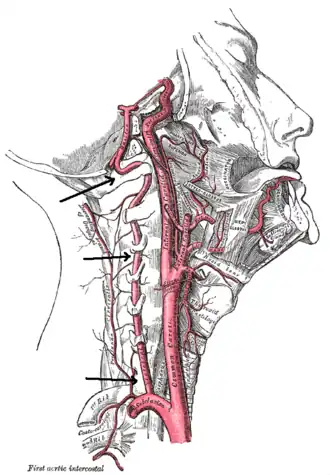

Angiografia por ressonância magnética dos vasos do pescoço numa pessoa com síndrome de Ehlers-Danlos tipo IV; A ressonância mostra uma dissecção da artéria carótida interna esquerda, dissecção de ambas as artérias vertebrais nos seus segmentos V1 e V2 e uma dissecção do terço médio e distal da artéria subclávia direita. Esses episódios marcantes de dissecção são típicos desse subtipo "vascular" da síndrome de Ehlers-Danlos.

Existem várias modalidades de diagnóstico para demonstrar o fluxo sanguíneo ou a ausência dele nas artérias vertebrais. A principal é a angiografia cerebral (com ou sem angiografia de subtracção digital).[3][13][14] Isto envolve a punção de uma grande artéria (geralmente a artéria femoral) e o avanço de um cateter intravascular através da aorta em direcção às artérias vertebrais. Nesse ponto, é injectado radiocontraste e o seu fluxo a jusante é capturado na fluoroscopia (imagem contínua de raios-X). O vaso pode parecer estenótico (estreito, 41–75%), ocluído (bloqueado, 18–49%) ou como um aneurisma (área de dilatação, 5–13%).[1] A angiografia cerebral é um procedimento invasivo e requer grandes volumes de radiocontraste, o que pode causar complicações como nefropatia induzida por contraste.[15] A angiografia também não demonstra directamente o sangue na parede do vaso, ao contrário das modalidades mais modernas.[2] O único uso restante da angiografia é quando o tratamento endovascular é contemplado.[1]

Os métodos mais modernos envolvem angiografia por tomografia computorizada, denominada angiotomografia (ATC ou angio-TC) — e ressonância magnética (RM). Estes métodos requerem uma menor quantidade de contraste e não são invasivos. A angiografia por TAC e a angiografia por RM são mais ou menos equivalentes quando usadas para diagnosticar ou excluir uma dissecção da artéria vertebral.[13] A ATC tem a vantagem de mostrar certas anormalidades mais cedo, tende a estar disponível fora do horário de expediente e pode ser realizada rapidamente.[1] Quando a angiografia por RM é usada, os melhores resultados são obtidos no cenário T1[2] usando um protocolo conhecido como "supressão de gordura".[3] A ecografia Doppler é menos útil, pois fornece poucas informações sobre a parte da artéria próxima à base do crânio e no forame vertebral, e qualquer anormalidade detectada na ecografia ainda exigiria confirmação através de um TC ou RM.[1][2][3]